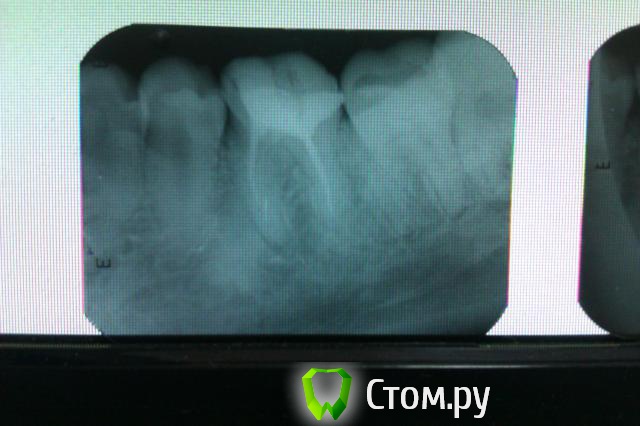

Как мне сказали несколько врачей, у меня цементома (снимок прилагается). Как я поняла, на корне 6-го зуба цементома, но это не все проблемы, 6-ой зуб был пролечен, удалены нервы и поставлены штифты, зуб отреставривован. После того как его сделали (цементому не трогали, сказали что не нужно ее трогать), зуб и челюсть болели недели три, потом прошло все. Но со временем начало болеть, не острой болью, а постоянной ноющей, появилась чувствительность у самого отреставрированного зуба, холод, тепло, прикосновения (хотя нерв удален), а еще начал он шататься. Зуб лечился где-то в мае этого года, а сейчас уже ноябрь. Что делать с ним? Снимки сделаны вчера 20.11.2013.

Добрый вечер. В зубе каналы пролечены не полностью. Очаг воспаления костной ткани в области переднего корня. Требуется удаление пломбы, исключение возможной трещины дна полости зуба, ревизия каналов и последующее покрытие коронкой.